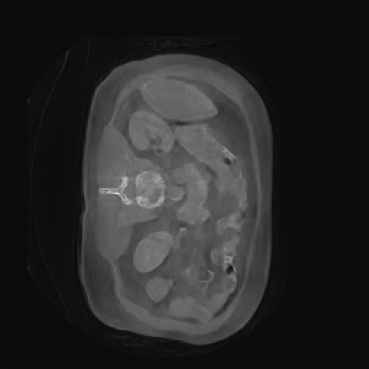

As shown in Figure 5, the generated slices exhibit high consistency across adjacent slices. The anatomical structures and semantic patterns are smoothly and coherently preserved between slices, indicating that our model is capable of generating 3D-consistent synthetic images rather than isolated 2D slices.

In our approach, we employ a compression factor of 4 to encode 3D medical images into the latent space. This level of compression reduces the spatial resolution of the original image (e.g., from 256×256 to 64×64 per slice), while still preserving the essential anatomical structures and semantic content. The latent representation at this scale offers a favorable trade-off between dimensionality reduction and semantic fidelity. Specifically, although fine-grained textures are simplified, key structural patterns (e.g., organ boundaries, lesion shapes) remain visually distinguishable and semantically coherent. As the compression rate increases, the latent representations become progressively more abstract. With lower compression (e.g., 2× or 4×), the latent features preserve key anatomical structures and spatial layouts, making them beneficial for our semantic image synthesis task in latent space, as the model can operate on compressed representations that retain sufficient semantic information without being overwhelmed by high-frequency noise. In contrast, higher compression rates (e.g., 8× or above) lead to a loss of fine-grained details and reduced semantic fidelity. The choice of a 4× compression thus ensures that the latent features are compact and meaningful, facilitating effective conditional generation while significantly reducing computational overhead. We therefore adopt a 4× compression as a compromise between computational efficiency and semantic preservation. The corresponding 2D slices in image space and latent space are shown in Figure 7.